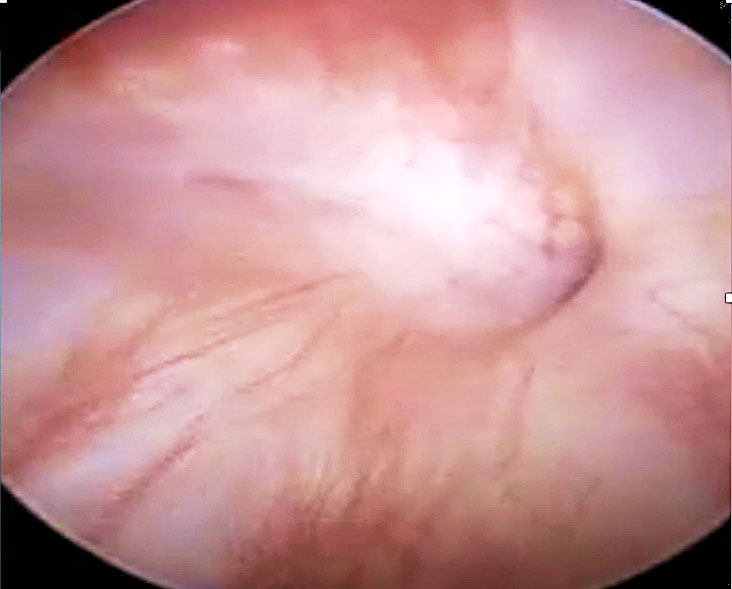

Late bladder or ureteric injury ~ fistula

Bladder injuries are often detected only a few days to a week postoperatively. A three-swab test using diluted methylene blue instilled into the bladder via a catheter can help confirm the presence of an injury. Alternatively, cystoscopy can be used to assess the site, size and proximity of the injury to the ureteric orifices.

A unique laparoscopic technique for VVF repair involves passing a ureteric catheter through the vaginal opening of the fistula and retrieving it cystoscopically through the urethra. The two ends of the catheter are tied together, eliminating the need for a catheter within the bladder during dissection. Laparoscopic dissection is then performed, carefully separating the tissue planes laterally until the fistula is visualized, guided by the ureteric catheter. Adequate dissection distal to the fistula opening is essential to mobilize enough healthy bladder tissue for closure. Once this is achieved, the ureteric catheter is cut and removed. The vaginal side of the fistula is closed using interrupted 1–0 Vicryl sutures. The bladder defect is then closed in two layers: a continuous suture with V-Loc, followed by a second layer of interrupted 1–0 or 2–0 Vicryl sutures (Figure 20). If necessary, the bladder can be filled with 200–250 ml of diluted methylene blue to test for leakage.

Finally, a Foley catheter is placed per urethra for 3 weeks before removal.